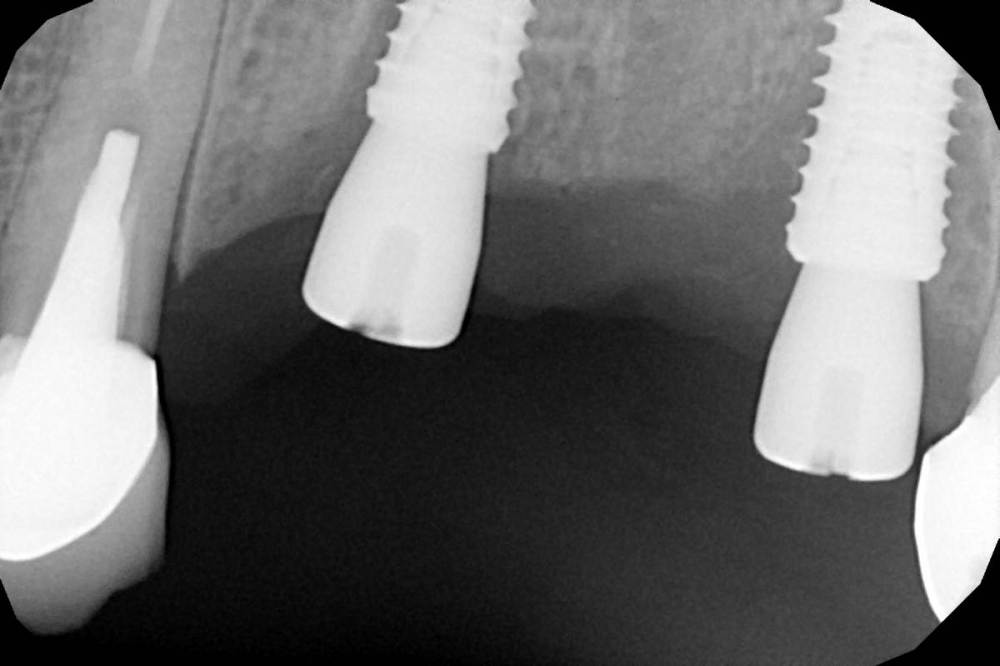

Женька Опубликовано 19 апреля, 2021 Автор Поделиться Опубликовано 19 апреля, 2021 Rg Ссылка на комментарий

Женька Опубликовано 21 июля, 2021 Автор Поделиться Опубликовано 21 июля, 2021 3 месяца минуло... клык на торке 30 неприятные ощущения второй премоляр на 10 и подвижность... отправил на кт. Всё насмарку... Ссылка на комментарий

Борис80 Опубликовано 21 июля, 2021 Поделиться Опубликовано 21 июля, 2021 премоляр в любом случае недозаглубитом болеет... Ссылка на комментарий

Irouil Опубликовано 21 июля, 2021 Поделиться Опубликовано 21 июля, 2021 1 час назад, Борис80 сказал: премоляр в любом случае недозаглубитом болеет... На момент установки не болел 3 часа назад, Женька сказал: Всё насмарку... Сочувствую Ссылка на комментарий